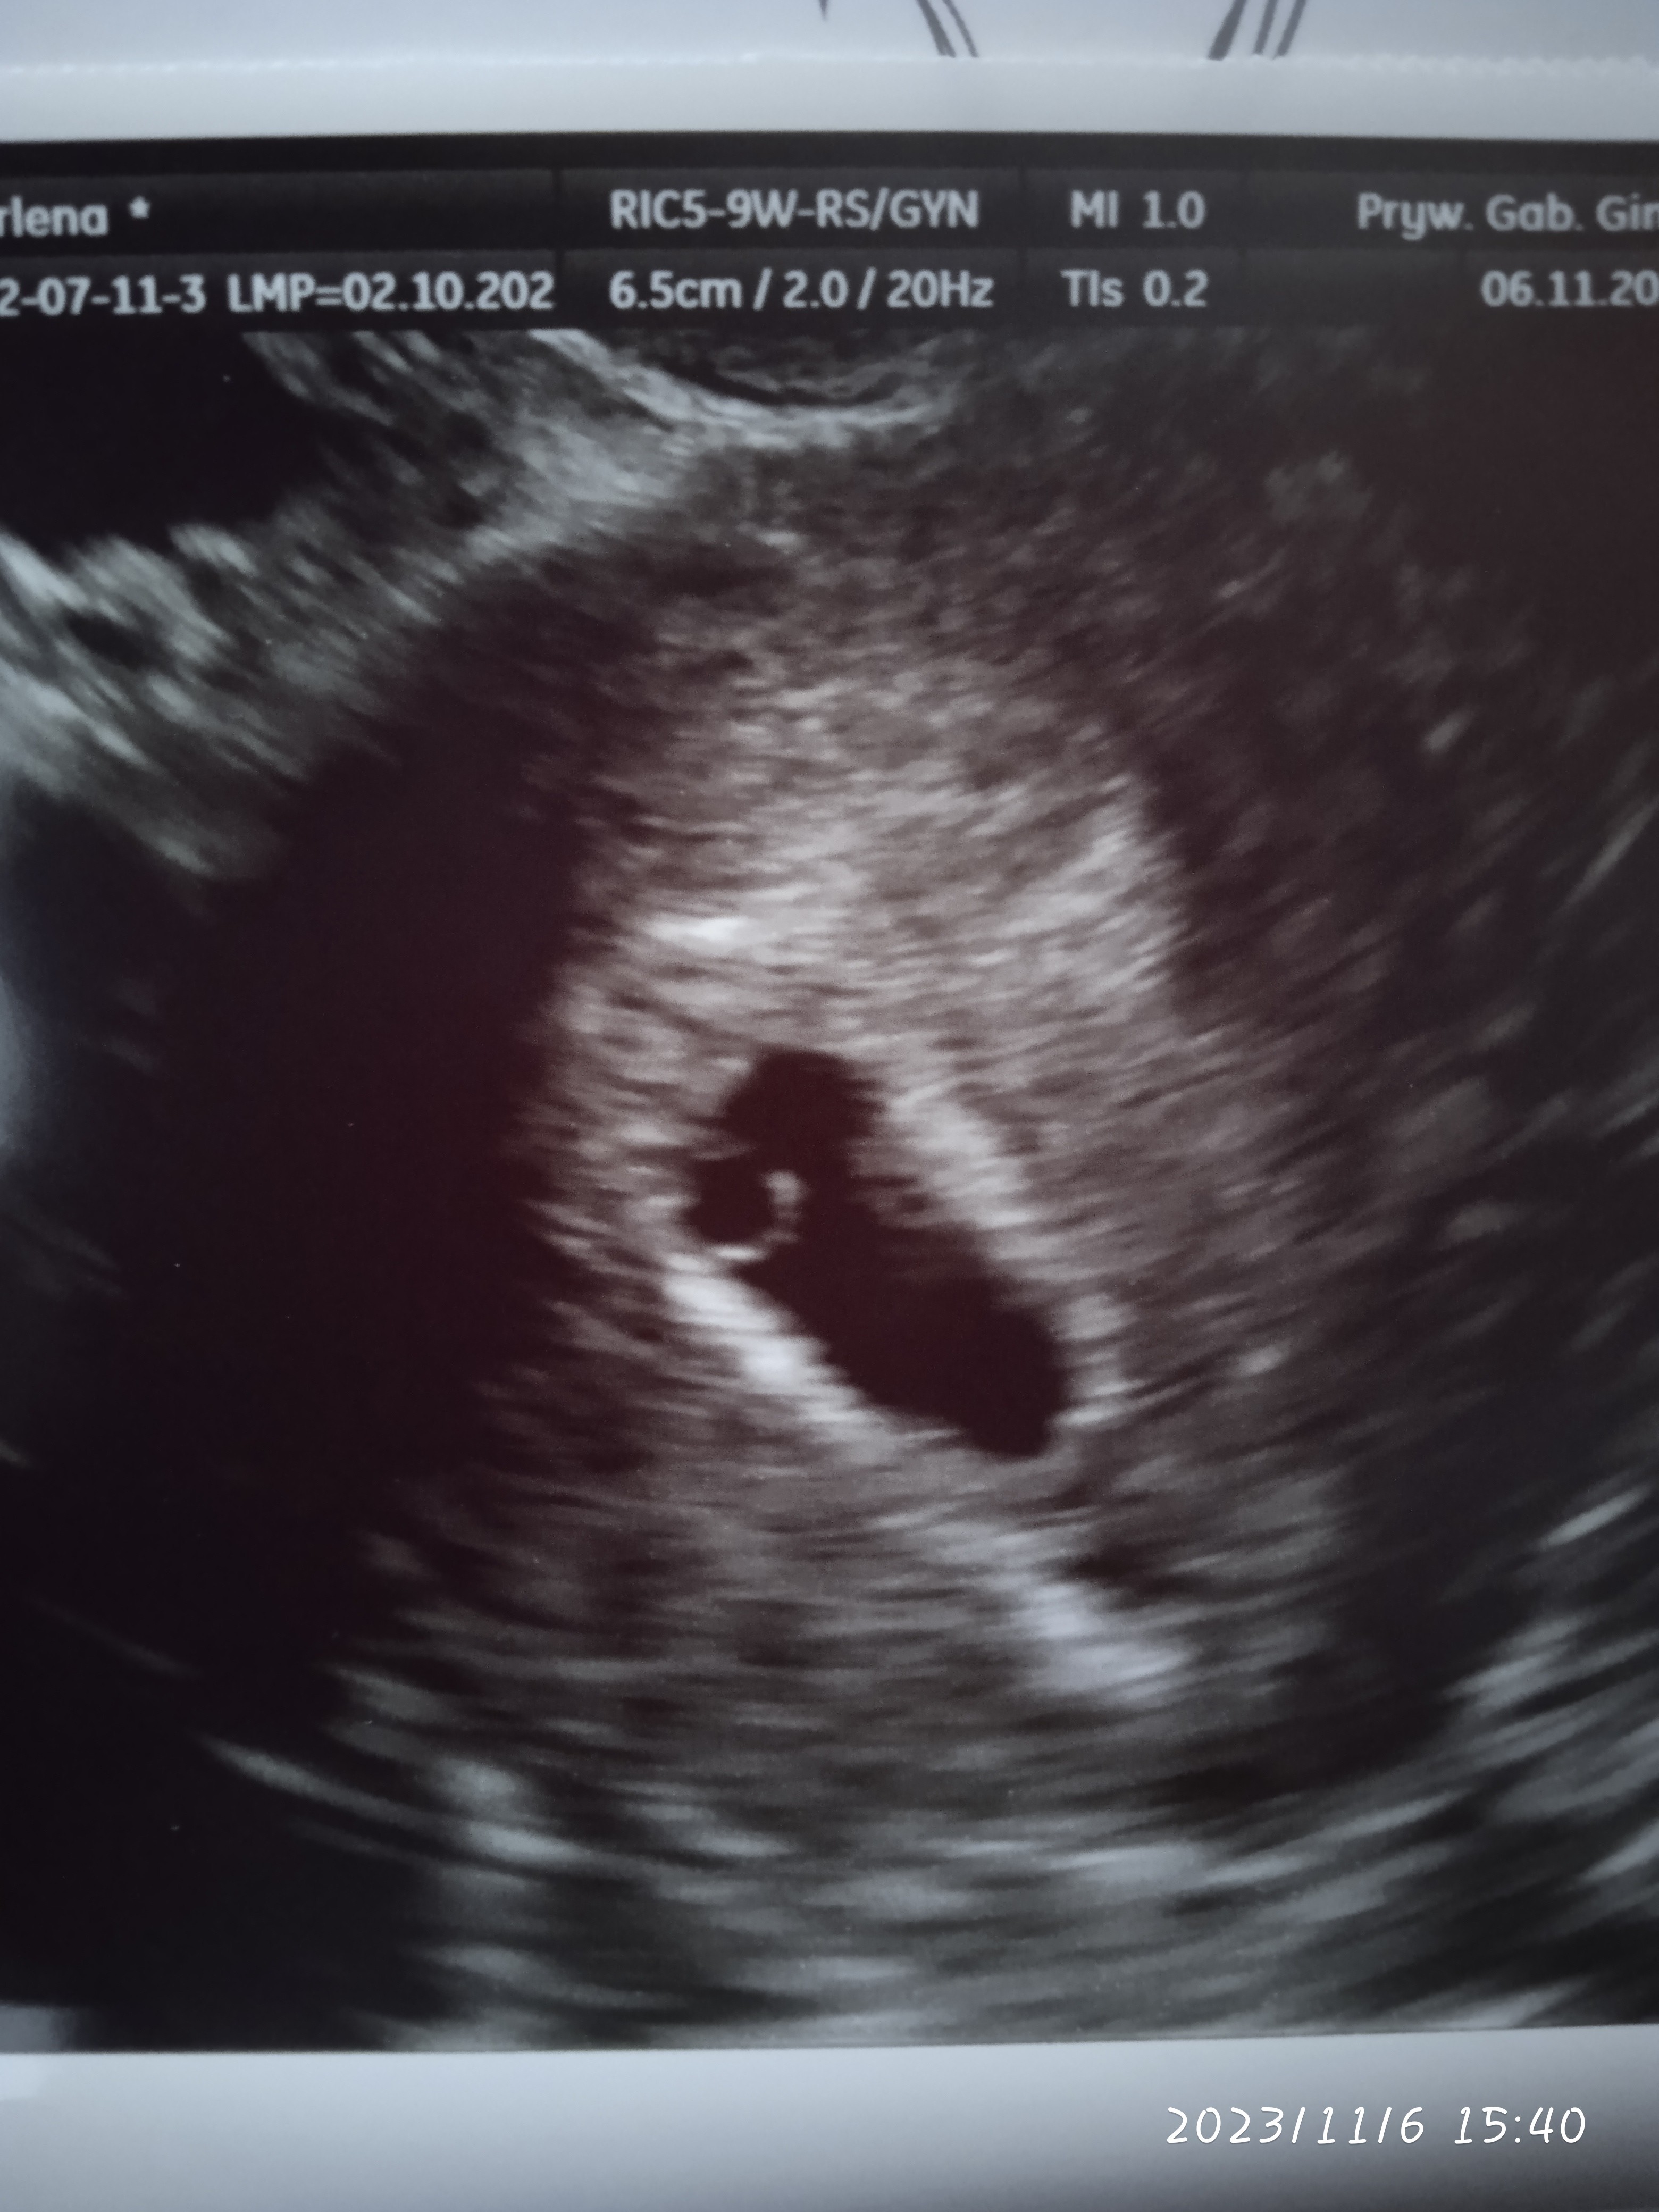

No i Kropka❤️

Załączniki

• IMG_20231106_154019.jpg

IMG_20231106_154019.jpg

1,2 MB · Wyświetleń: 122